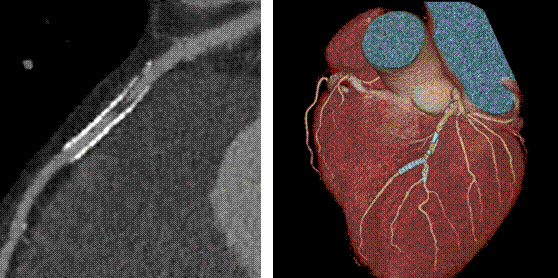

新技術(shù)介紹一:能譜曲線鑒別病灶同源性

能譜曲線體現(xiàn)了不同物質(zhì)對X線的吸收程度,從而體現(xiàn)了物質(zhì)本身的結(jié)構(gòu)特性。從以下的糖水及鹽水的例子可以看出,在常規(guī)CT上表現(xiàn)為同樣CT值-即無法區(qū)分的糖鹽水卻表現(xiàn)為完全不一樣的能譜曲線,從而讓我們可以區(qū)分它們。

同樣,對于常見的胸水的病理類型為滲出液還是漏出液,也可以通過能譜曲線進行鑒別。

除以上應(yīng)用之外,能譜曲線還應(yīng)用在鑒別腫瘤原發(fā)灶和轉(zhuǎn)移灶的關(guān)系。